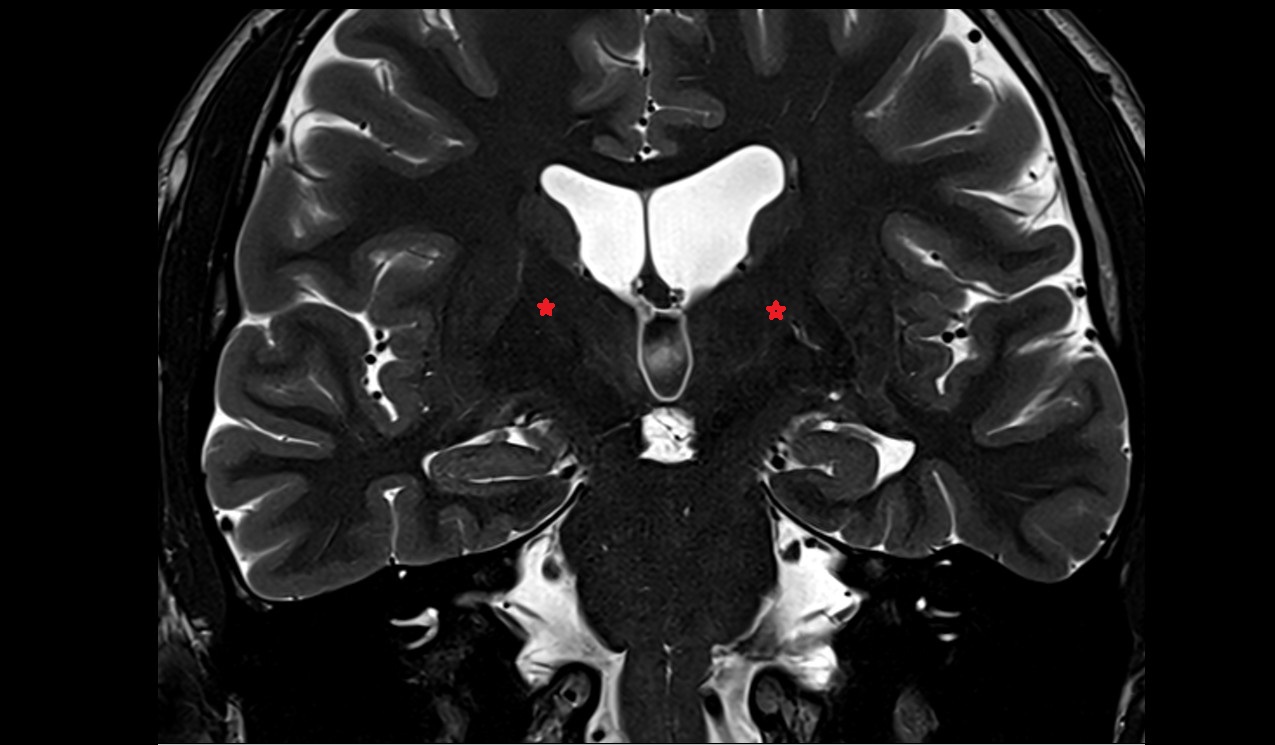

- Hippocampus